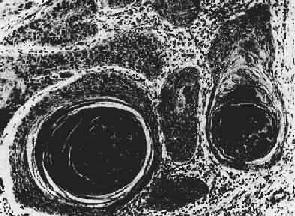

图7-13 腺(胃)

细胞排列紊乱,多层,形成大小不等、形状不规则的腺样结构,浸润于胃壁组织内